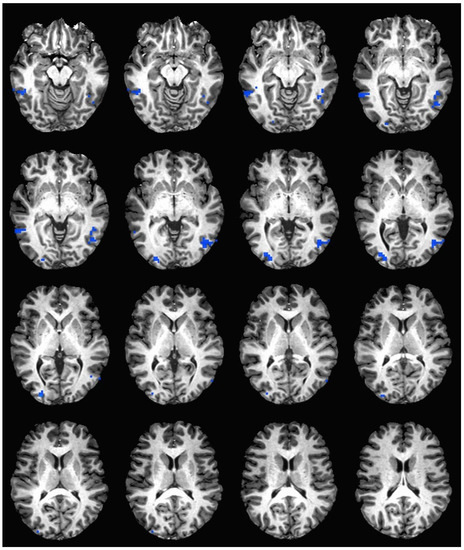

During the hedonic evaluation of saccharin, caffeine non-consumers had significantly lower neuronal activation than caffeine consumers in the middle temporal gyrus, inferior temporal gyrus, middle occipital gyrus, right fusiform gyrus, right lingual gyrus, and right cuneus (See Table 5 and Figure 3).

Figure 3. Brain activation during the hedonic evaluation of saccharin. Blue indicates areas where caffeine consumers had significantly greater activation in comparison to caffeine non-consumers.

Both sides of the medial frontal gyrus were significantly activated in caffeine non-consumers during the hedonic evaluation of caffeine and sucrose, but not in the saccharin condition. Previous studies have linked activation in the left dorsolateral prefrontal cortex to processing and rating multimodal flavor stimuli [55]. Further, this is an area where the consequences of actions directly affect cognition in the preparation for and selection of response [55]. Results suggest a greater cognitive effort during the hedonic evaluation of caffeine and sucrose for caffeine non-consumers and during saccharin for caffeine consumers in information processing pathways coinciding with results previously stated. Due to the variability in between group activation within information processing areas, it is difficult to make a conclusive decision whether or not caffeine non-consumers activate a larger network than consumers in order to perform the hedonic evaluation task. While there was primarily more activation within the overall study in caffeine non-consumers, caffeine consumers demonstrated greater activation during the saccharin condition. We speculate that greater activation for caffeine consumers during saccharin evaluation may have occurred because saccharin evokes both sweet and bitter taste [56]. In addition to the stimulation of both sweet and bitter receptors, additional expenditure of cognitive effort may be required to hedonically evaluate this taste experience.